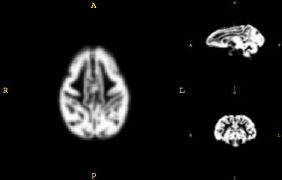

• Develop a juvenile WM/GM/CSF atlas from normal subject images.

• The atlas construction procedure was adapted from Automatic brain segmentation in rhesus monkeys; M. Styner, R. Knickmeyer, S. Joshi, C. Coe, S. J. Short, and J. Gilmore. Proc SPIE Vol 6512 Medical Imaging 2007, pp 65122L-1 - 65122L-8.

Images